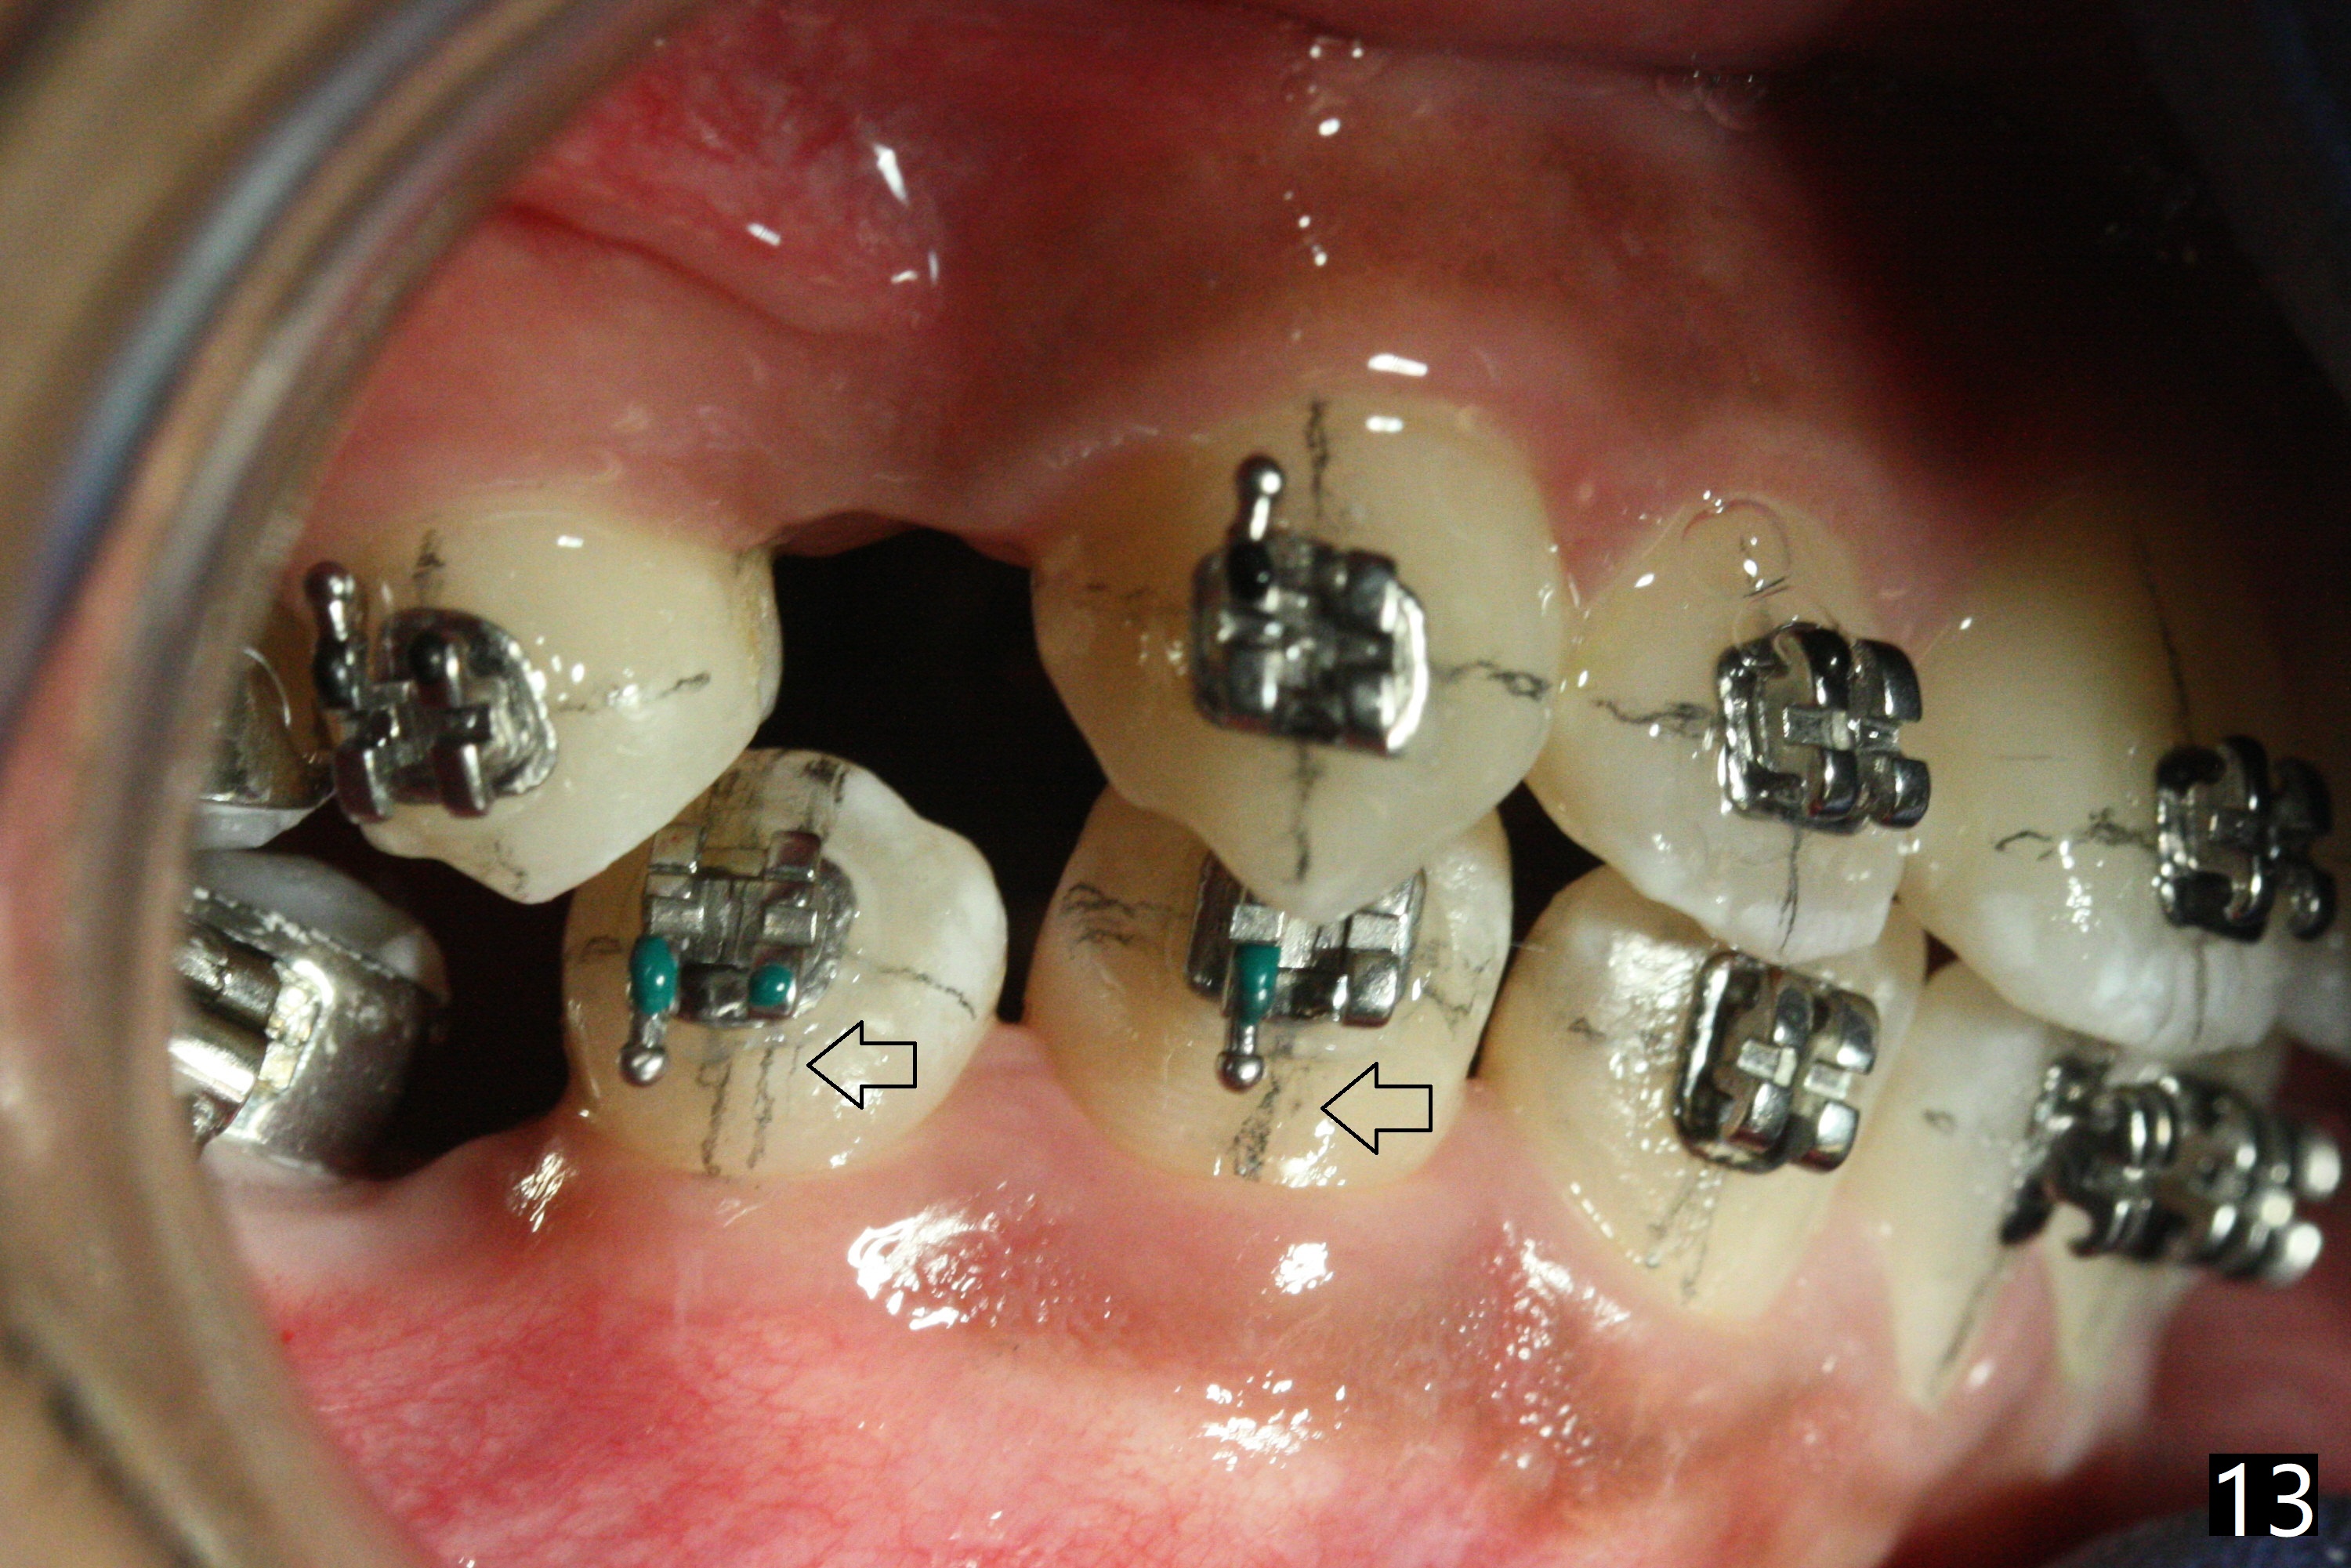

In fact, automatic shifting is striking.  For example, UR5 lingualization (Fig.12 arrow) makes it easy to insert 12 niti wire.  Distalization of the lower bicuspids and canine is more obvious (Fig.13,14 arrows) than the upper counterparts.  Because of incomplete eruption, it is difficult to band L7s; instead brackets are placed (Fig.15-17).  The purpose of LR one is to facilitate LR6 buccalization (Fig.15,16), whereas LL one to correct rotation of itself (Fig.17).